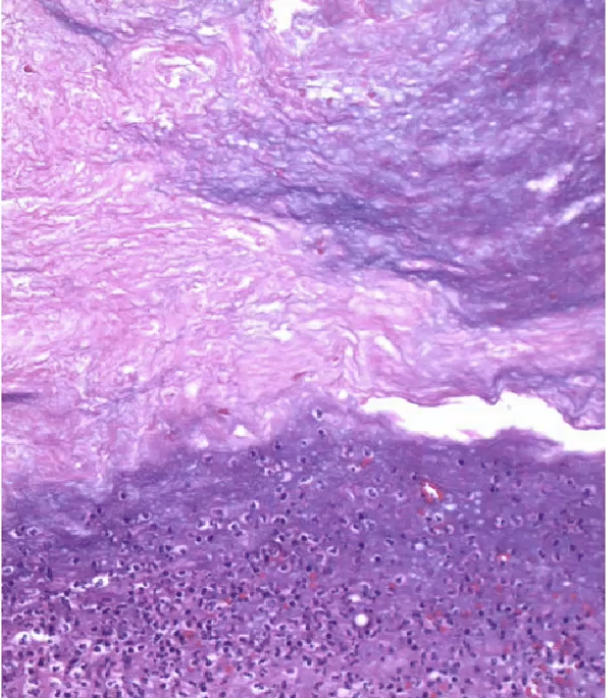

Chronic cholecystitis

Rokitansky-Aschoff Sinuses

small pouches that form in the gallbladder wall, often associated with chronic cholecystitis. They can contribute to inflammation and dysmotility of the gallbladder.